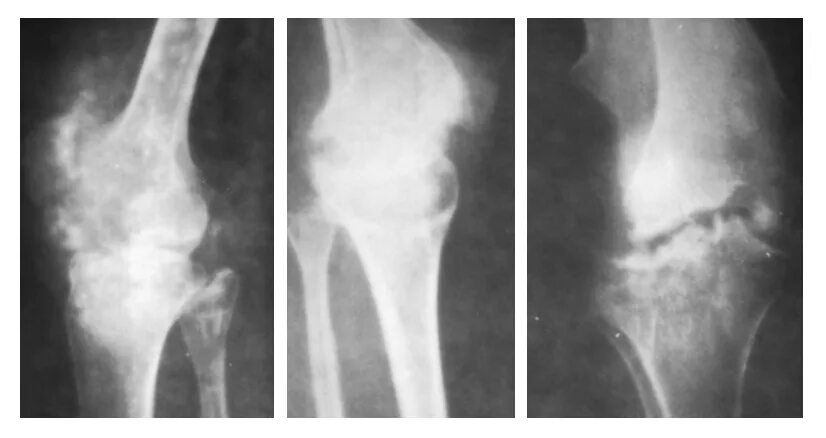

Туберкулез суставов симптомы